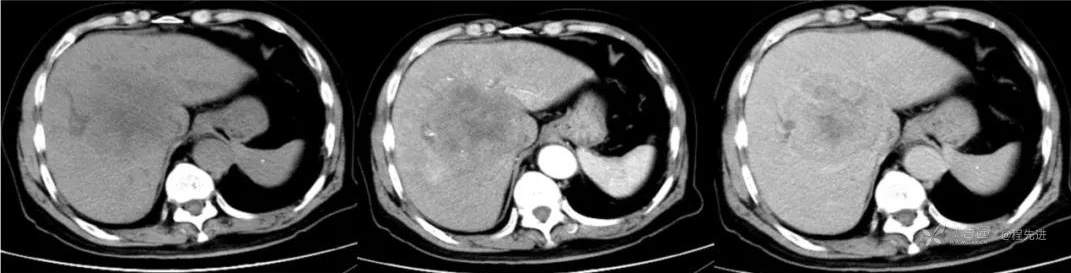

红五月特别精彩病例|胸部不适CT检查发现肝门区占位【病理已公布】

简要病史:因胸部不适入院,胸部CT示:肺部感染性病变;腹部CT示:肝门区占位性病变

既往史:有乙型肝炎病毒感染病史,未接受系统治疗

辅助检查:白细胞12.33×10^9/L 谷丙转氨酶 70u/L 谷草转氨酶90u/L